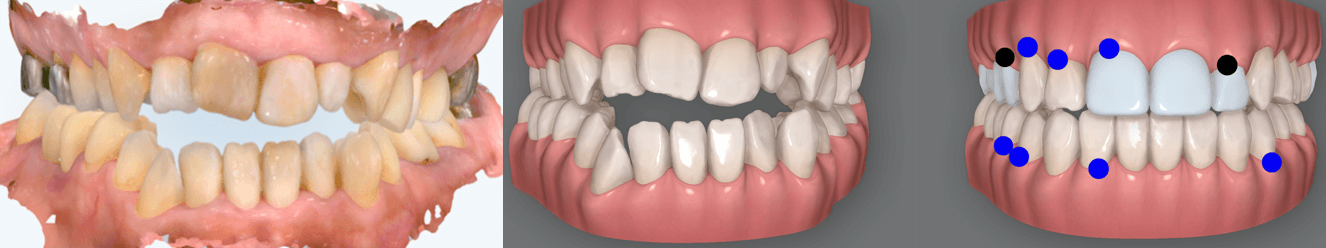

当院では、体の歪みを調べ、その方にとって無理のない安定した顎位を見つけ出し、その位置で噛み合わせを構築することを重要視した矯正治療を行っています。

また、歯列矯正だけではなく、全顎的に歯の治療(補綴治療)を必要とする方も体の歪みをみる上で治療をすることがとても重要です。